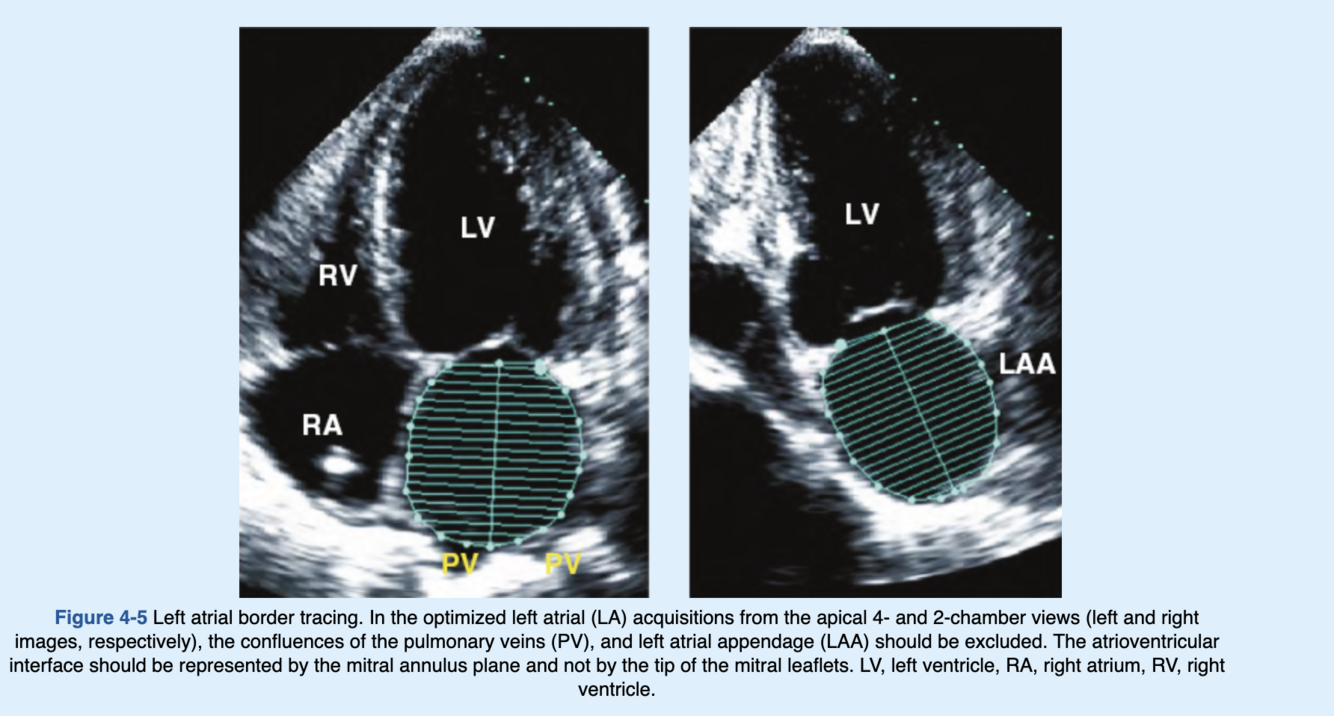

How to accurately trace the LA border?

When tracing the borders of the left atrium, the confluences of the pulmonary veins, and LA appendage should be excluded. The atrioventricular interface should be represented by the mitral annulus plane and not by the tip of the mitral leaflets